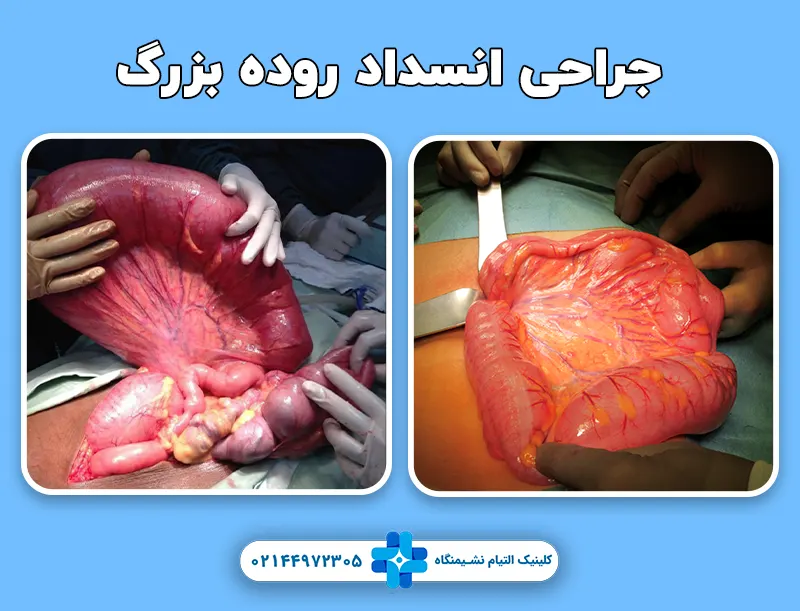

درمان جراحی

روش جراحی به شدت و نوع انسداد بستگی دارد. بر اساس شدت عارضه از جراحی باز، لاپاروسکوپی و جراحی با استفاده از استنت برای درمان این بیماری استفاده می شود.